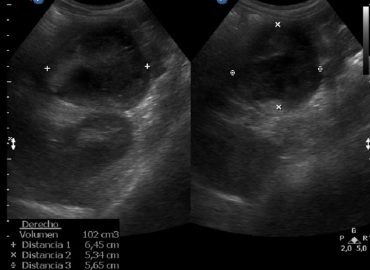

Niño de 3 años, sin antecedentes previos. Motivo de consulta: fiebre y disuria de 5 días de evolución Ecografía renovesical […]